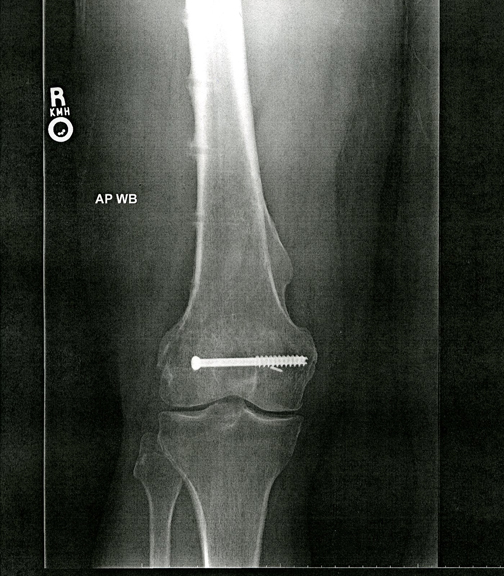

To the left is an x-ray of my leg as it has been since January, 2002.  The bracket depicted above was attached to my right femur with numerous screws to stabilize it during the original recovery period.  To the right is an x-ray of my leg today (literally, it was taken today, September 2, 2014).  The one remaining screw was so deeply embedded that my surgeon couldn't remove it.  He said that should knee replacement surgery become necessary, that's when it will go.  In the meantime it's an interesting if inaccessible souvenir.